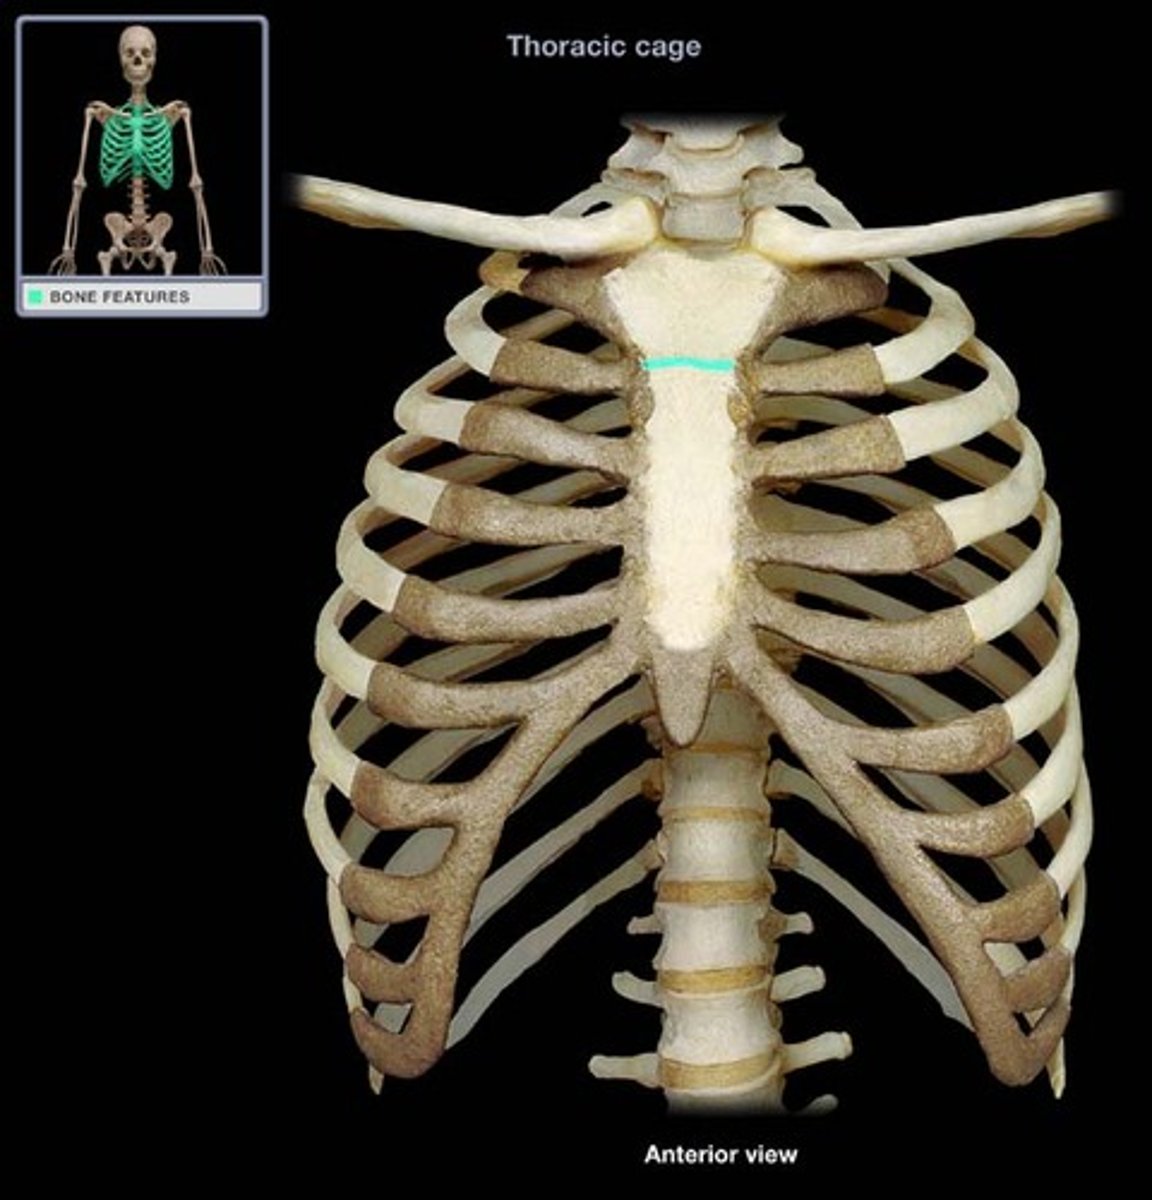

What makes up the thoracic cage?

sternum, ribs, and thoracic vertebrae

manubrium of sternum

suprasternal (jugular) notch

sternal angle

Xiphoid process of sternum

(T10)

Midline marker for superior level of liver, central tendon of diaphram

inferior border border of heart

cartilaginous in young people. Bone after 40.